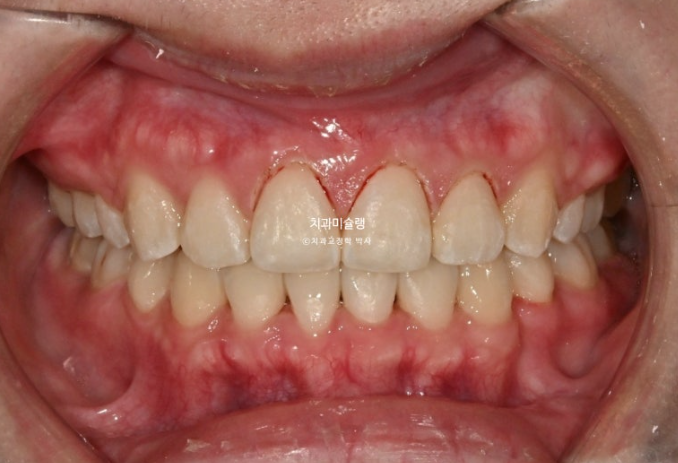

중심선은 잘 맞고 과개교합도 해소가 되었습니다.

어금니 교합은 물샐틈 없는 1급 교합관계 입니다.

이제 전 후 비교볼게요.

총 치료기간은 2년 3개월 입니다.

깊게 물리는 과개교합이 개선이 되면서 아래 앞니가 비로소 잘 보입니다.

앞니 함입과 잇몸성형의 합작으로 드라마틱하게 개선이 된 잇몸미소 거미스마일 교정

옥니였던 위 앞니 각도가 개선이 되면서 미소가 한층 밝아졌습니다.